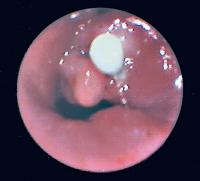

Trachea - Stenose

Abbildung 7: Blick in die Trachea auf eine Stenose nach chirurgischer Tracheotomie. Sichtbare Fadenreste.

Keywords: Bronchoskopiechirurgische TracheotomieKardiologieStenoseTrachea